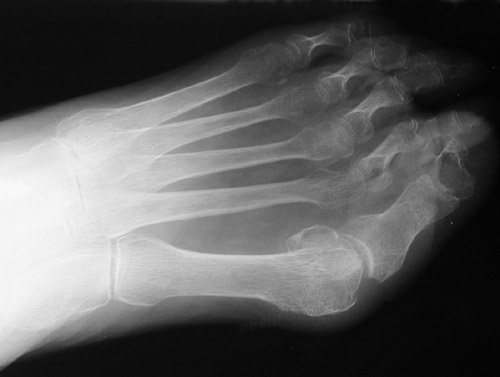

Both feet shown here reveal a deformity known as a bunion in which the first metatarsophalageal joint of the foot becomes very angled and prominent. This deformity produces difficulty in ambulating and in fitting shoes.